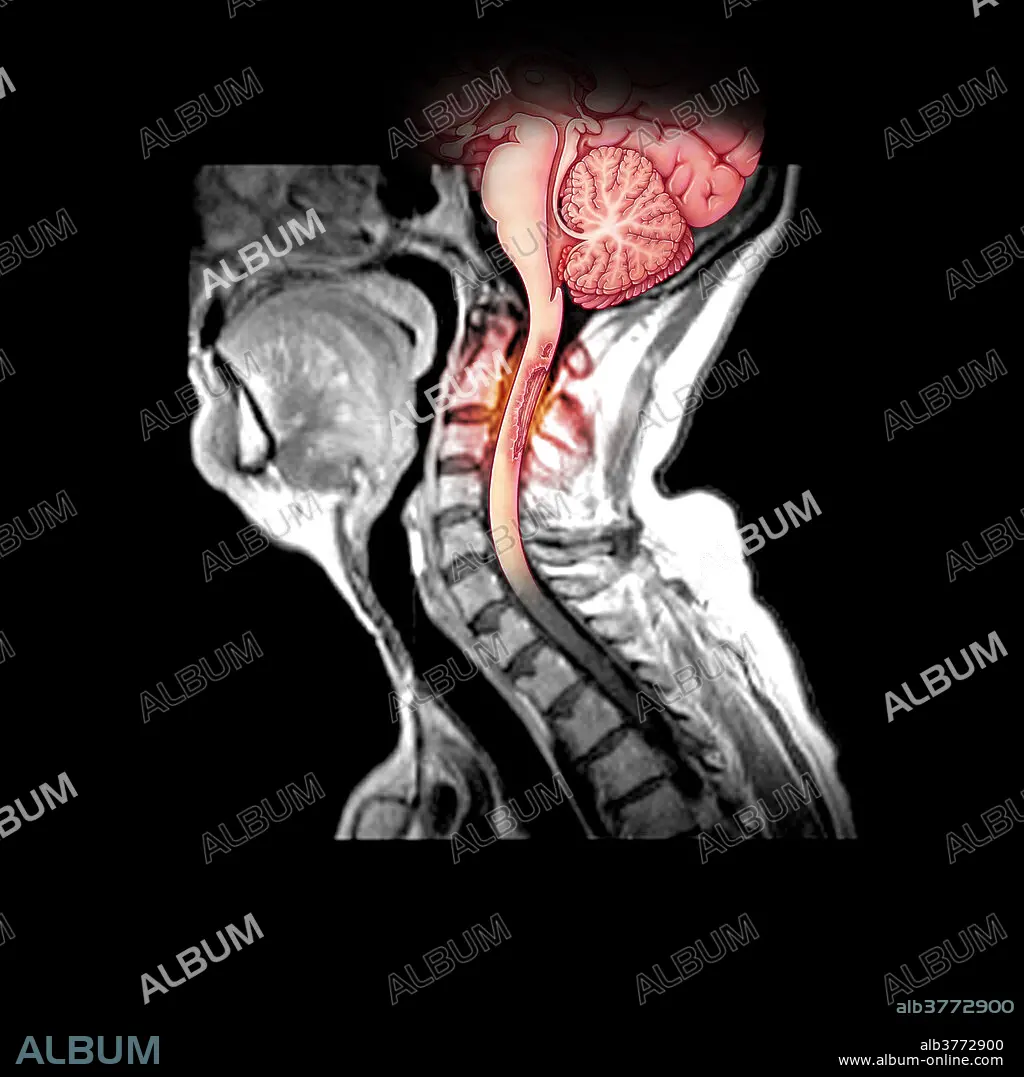

Demyelination of Spinal Cord in MS

This composite illustration of a MRI of the cervical spine/spinal cord shows an area of pathologic enhancement along the posterior (dorsal) aspect of the upper cervical spinal cord. This is in a patient with multiple sclerosis and represents areas of active demyelination.

Title: Demyelination of Spinal Cord in MS

Caption: This composite illustration of a MRI of the cervical spine/spinal cord shows an area of pathologic enhancement along the posterior (dorsal) aspect of the upper cervical spinal cord. This is in a patient with multiple sclerosis and represents areas of active demyelination.